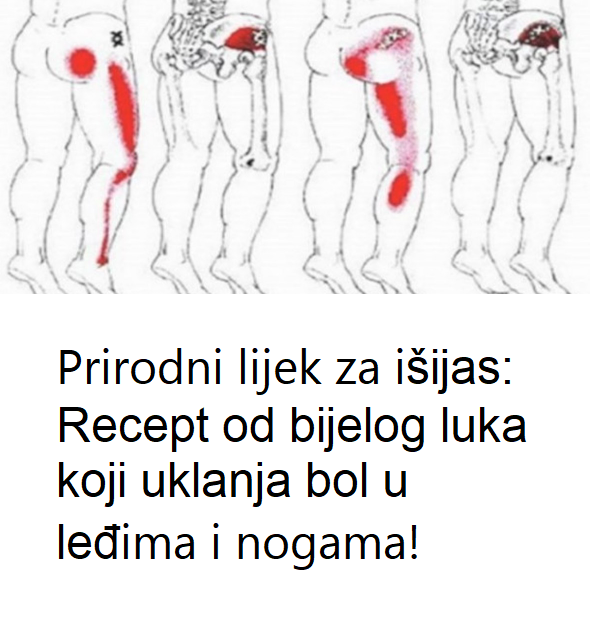

🩻 Simptomi išijasa

Ako niste sigurni da li vaš bol potiče od išijasa, obratite pažnju na ove simptome:

Bol koji počinje u donjem dijelu leđa ili kuku i širi se niz nogu.

Peckanje ili utrnulost u nozi.

Bol se pogoršava prilikom sjedenja.

Slabost ili poteškoće u pomjeranju noge ili stopala.

Iznenadni probadajući bol pri pokretu.

Konstantan bol u predjelu zadnjice.